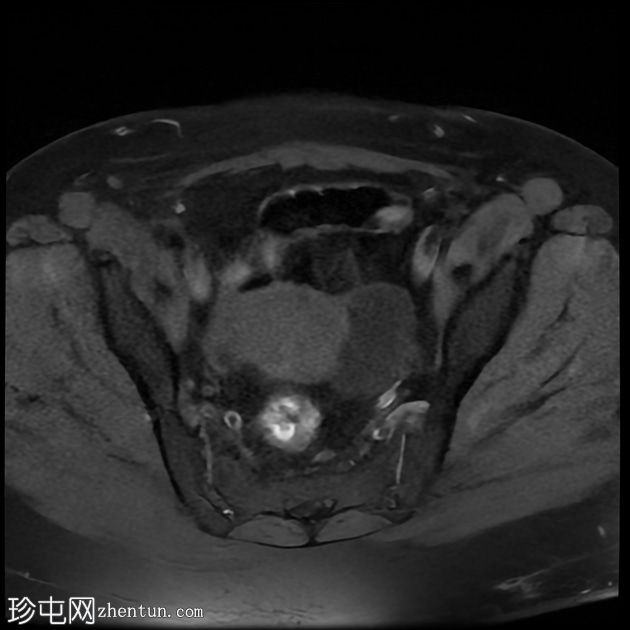

轴位

T1加权像

左侧卵巢增大,呈弥漫性低T1信号和高T2信号,可见周边卵泡,部分卵泡除周边卵泡周围有环状强化外,无明显实质强化。左侧附件蒂呈漩涡状,提示卵巢扭转。